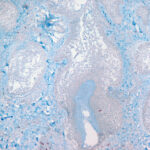

The mucin found in these six diseases represents an increase in the mucin that is normally present in the ground substance of the dermis. It consists of proteins bound to hyaluronic acid (hyaluronan), which is an acid mucopolysaccharide or glycosaminoglycan. As a result of the great water-binding capacity of hyaluronic acid, dermal mucin contains a considerable amount of water. This water is largely removed during the process of dehydration of the specimen; consequently, in routine sections, the mucin, because of its marked shrinkage, appears largely as threads and granules. |

The mucin present in the six types of mucinosis stains a light blue in sections stained with H&E. It also stains with colloidal iron. It is Alcian blue-positive at pH 2.5 but negative at pH 0.5 and shows metachromasia with toluidine blue at pH 7.0 and 4.0 but no metachromasia below pH 2.0 . It is PAS negative (indicating the absence of neutral mucopolysaccharides) and aldehyde fuchsin negative (indicating the absence of sulfated acid mucopolysaccharides). The mucin is completely removed on incubation of histologic sections with testicular hyaluronidase for 1 hour at 37″C . |